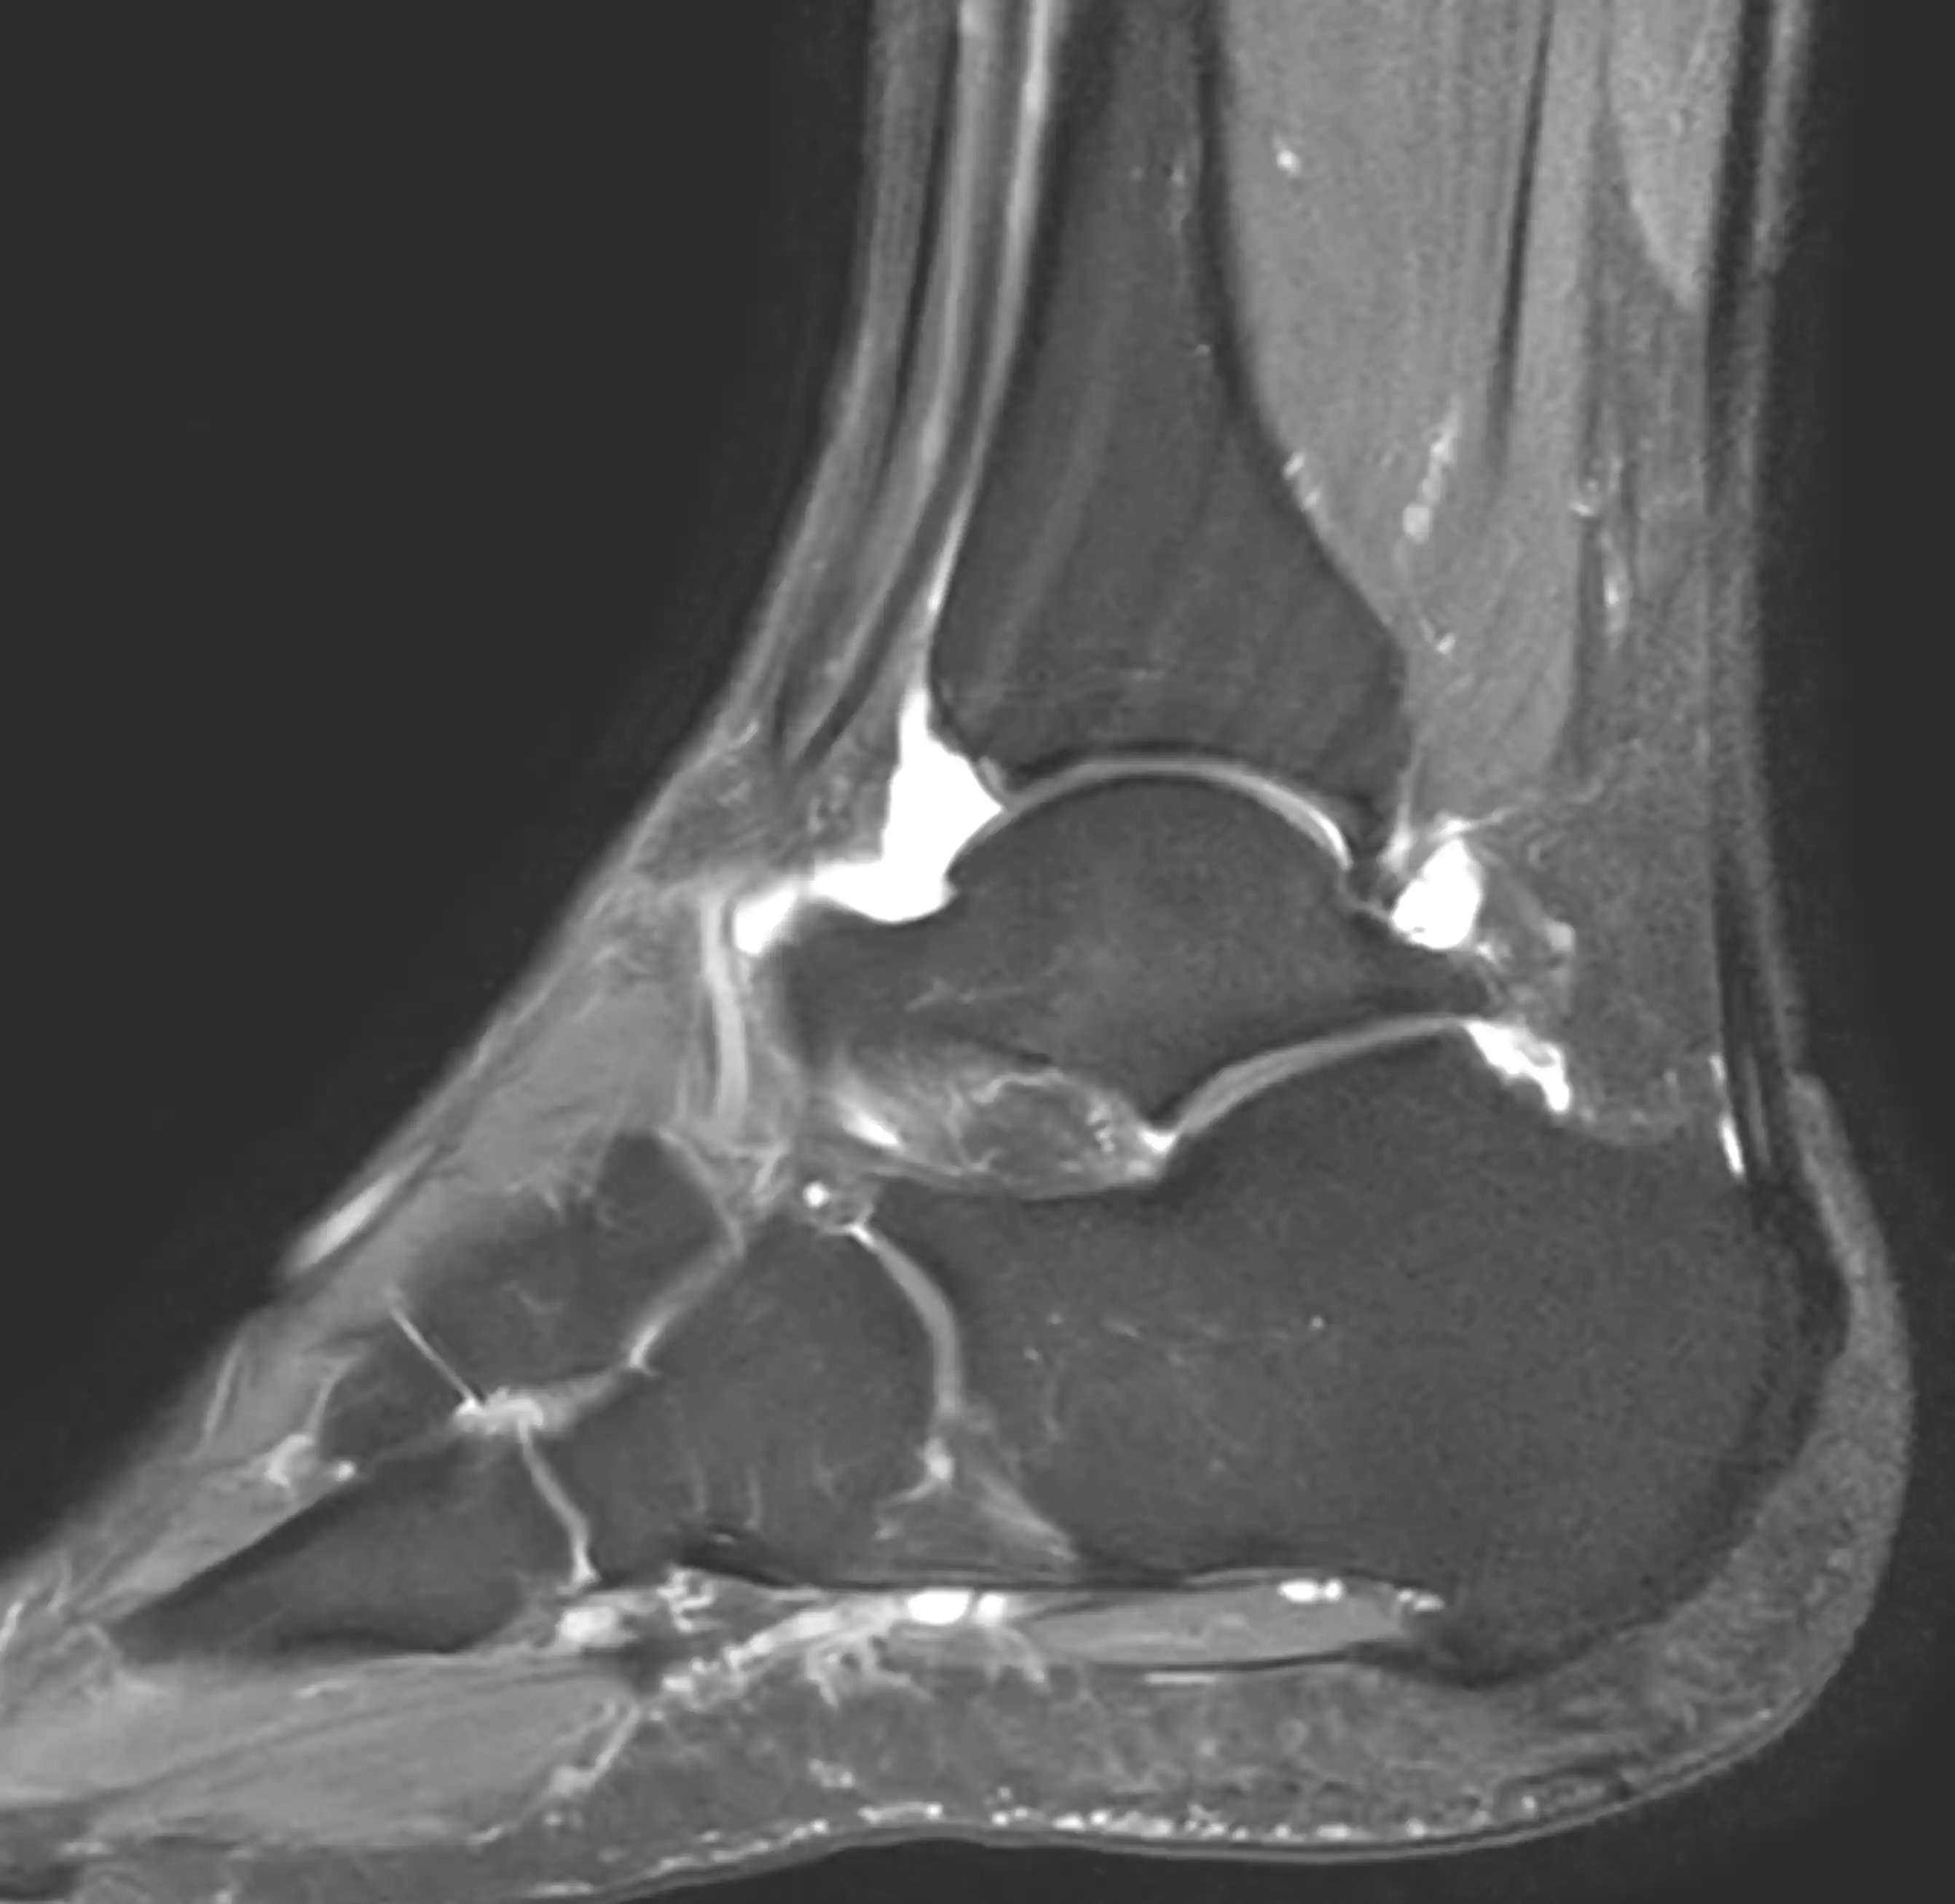

МРТ гомілково-ступневого суглобу — це сучасний та високоточний метод обстеження, який дозволяє детально оцінити стан кісток, зв’язок, сухожиль, хрящів та м’яких тканин у ділянці гомілково-ступневого суглоба.

Магнітно-резонансна томографія допомагає точно визначити причину болю в області стопи та гомілки без використання рентгенівського випромінювання.

Що показує МРТ гомілково-ступневого суглобу

МРТ дозволяє виявити:

- пошкодження зв’язок

- розриви сухожиль

- травматичні ушкодження суглоба

- запальні процеси

- дегенеративні зміни

- ушкодження хрящової тканини

- патології м’яких тканин

- новоутворення